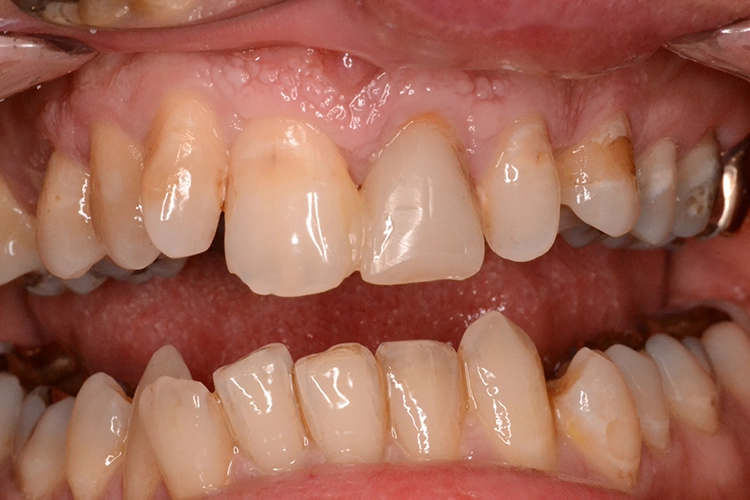

Bei diesem 49-jährigen, allgemeinanamnestisch unauffälligen Patienten liegen diverse ästhetisch störende Zahnstellungsanomalien vor, wobei Zahn 21 bei extremer Elongation frakturierte (Abb. 2a). Nach einer Übergangsversorgung mittels provisorischer Stiftkrone (Abb. 2b) entschied sich der Patient für eine Zahnentfernung bei gleichzeitiger Implantation. Im Ausgangs-DVT (Abb. 2c und d) zeigt sich im Cross-Sectional, wie weit der Processus alveolaris zurückliegt.